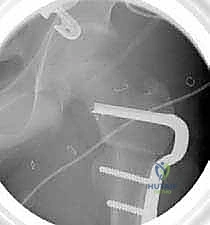

6. التثبيت الداخلي القوي (Internal Fixation)

لضمان التحام العظم في وضعه الجديد، يستخدم الدكتور هطيف نظام تثبيت عالمي يتمثل في صفيحة الشفرة الزاوية (AO 90-degree Blade Plate) أو مسامير وصفيحة مخصصة للأطفال. يتم إدخال الشفرة في عنق الفخذ، وتثبيت الصفيحة على جسم العظم باستخدام براغي معدنية قوية.